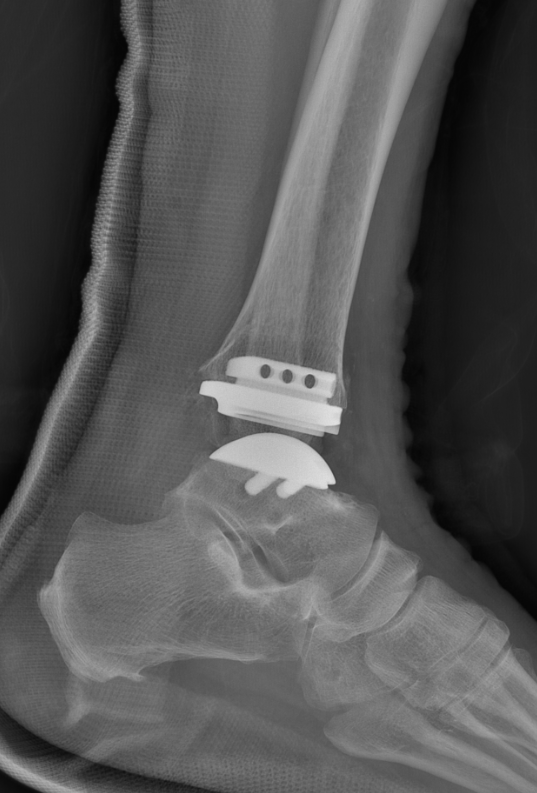

第一台手术的患者是位75岁的叔叔,被“脚脖子”痛缠了4年,疼得越来越厉害,病情已经到了严重阶段。

武勇主任团队给他做了3D打印导板辅助下人工全踝关节置换术。

这种手术适合踝关节病严重的患者,通过替换病变的关节结构,能帮着缓解疼痛、恢复关节活动,让老人日常走路更自在些。

术后侧位X线

术后正位X线